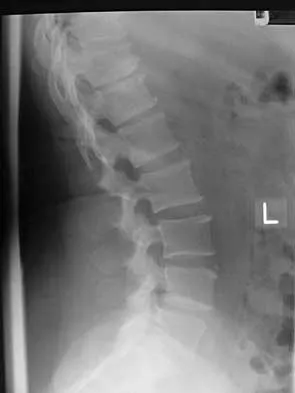

A 44-year-old woman has had lower extremity dysesthesias, urinary incontinence, and has been unable to walk for the past 2 days. She reports no pain or history of trauma. She notes that 3 weeks ago she missed work for 2 days because of back pain, but it resolved with rest. Examination shows decreased or absent sensation below the knees, no motor function below the knees, and decreased rectal tone. Catheterization results in a postvoid residual of 2,000 mL. Plain radiographs and MRI scans without contrast are shown in Figures 1a through 1d. What is the next most appropriate step in management?

Explanation

The patient has had a clear and sudden onset of a profound neurologic deficit. The radiographic studies suggest a lesion in the conus medullaris that appears to be intradural and intramedullary. MRI, with and without contrast, will best evaluate this mass further. The addition of gadolinium allows further evaluation of vascularity and the extent of the lesion. Eichler ME, Dacey RG: Intramedullary spinal cord tumors, in Bridwell KH, Dewald RL (eds): The Textbook of Spine Surgery, ed 2. Philadelphia, PA, Lippincott-Raven, 1997, vol 2, pp 2089-2116.